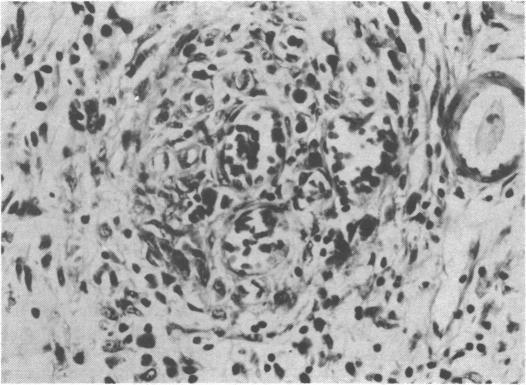

Acute abdomen in rheumatoid arthritis due to necrotizing arteritis.

Br Med J. 1973 Jun 9;2(5866):592-3. doi: 10.1136/bmj.2.5866.592.

Acute abdomen in rheumatoid arthritis due to necrotizing arteritis.类风湿关节炎所致坏死性动脉炎引起的急腹症。